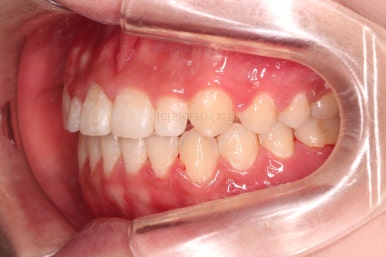

앞니 각도, 가지런한 느낌, 덧니 등 모든 점이 다 개선되었네요.

부산옥니교정 전후를 비교해 볼게요.

입안의 모습에서도 모든게 다 좋아졌고요.

웃는 모습과도 매우 조화롭게 치열이 가지런해졌네요.

앞니 각도가 개선되면서 웃을 때 보이는 치열도 가득차 보이고 환해보이고요.

다물었을 때의 옆모습도 약간 오목하던 입매가 볼륨감이 생기면서 훨씬 예뻐졌습니다.